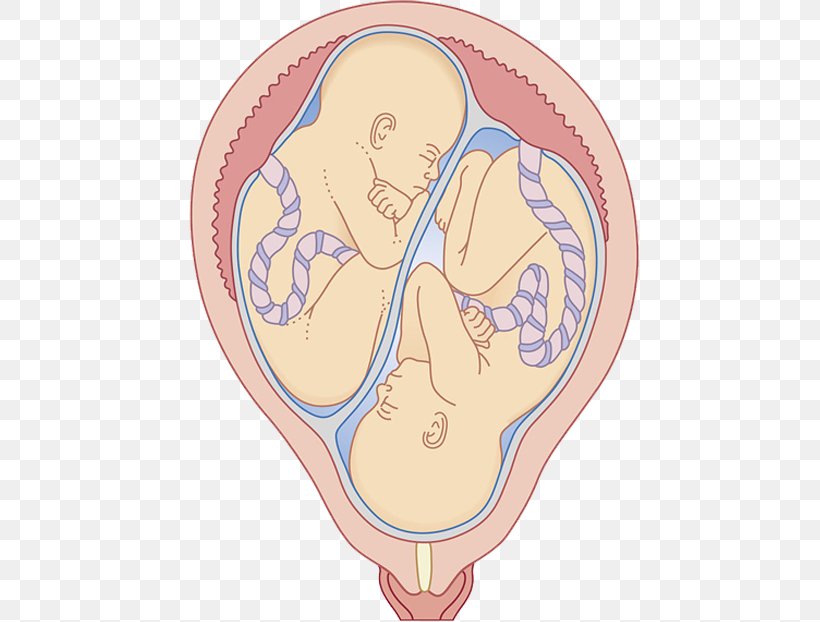

Иконки и символы, связанные с эмбрионом

Раздел: Образы вокруг